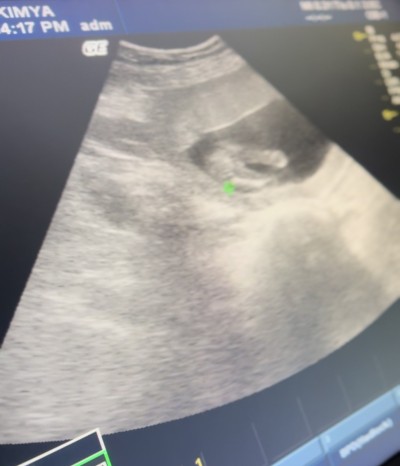

Kızlar cinsiyet tahmini yaparmısınız image

Gebelik haftası 16 haftalık

Erkek gibi ikinci fotoda çıkıntı var sanki, doktor tahminde bulunmadımı

Çıkıntı var gibi erkek

Çünkü bacak arasında bir çıkıntı var ikinci fotoğrafta siz görmediniz mi

Bence kız canım erkek bebekte çıkıntı farkı oluyor bu üç çizgiye benziyor yani kız

Evet bacak arasında çıkıntı var gibi , neyse önemli olan sağlıklı olması